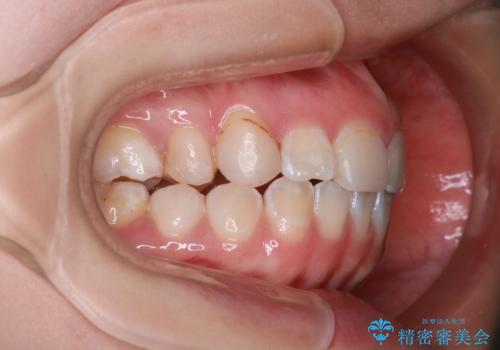

「フルリンガル矯正|アンカースクリューを活用し正中を整えた症例」

- 他院で矯正治療を受けていた患者様が、より理想的な仕上がりを求めて転院されました。主なお悩みは正中(前歯の中心)がズレていることで、歯並び全体をきれいに整えたいとのご希望でした。治療には舌側(裏側)に装置を装着するフルリンガル矯正を採用し、さらにアンカースクリューを用いて奥歯を後方へ移動(遠心移動)させることでスペースを確保し、正中を調整する計画を立てました。

矯正装置を装着し、アンカースクリューを活用しながら奥歯を少しずつ後ろへ動かし、正中を整えていきました。治療には時間がかかりましたが、計画通りに歯を移動させ、バランスの取れた歯並びへと仕上げることができました。裏側矯正のため、見た目を気にすることなく治療を進められた点も、患者様にとって大きなメリットでした。治療後は、「正中がしっかり合って、口元がスッキリした」とご満足いただきました。